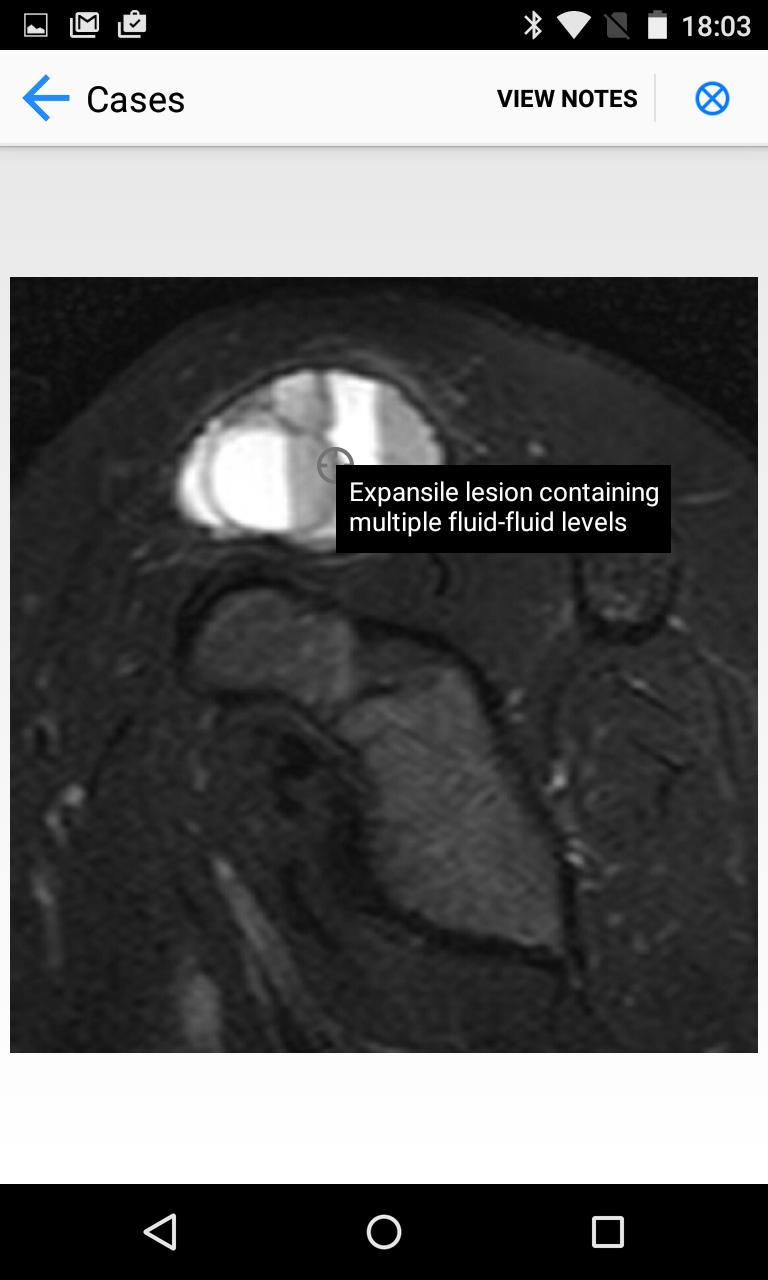

Estudios de caso de tumores de huesos y tejidos blandos. Una fuente de casos tumorales MSK/sarcoma.

BoSTT trae al usuario una experiencia real de casos frecuentes y raros, típicos y más inusuales de tumores de huesos y tejidos blandos. Cada caso tiene antecedentes clínicos, imágenes de radiología y patología de alta resolución, diagnóstico, tratamiento y puntos de aprendizaje.